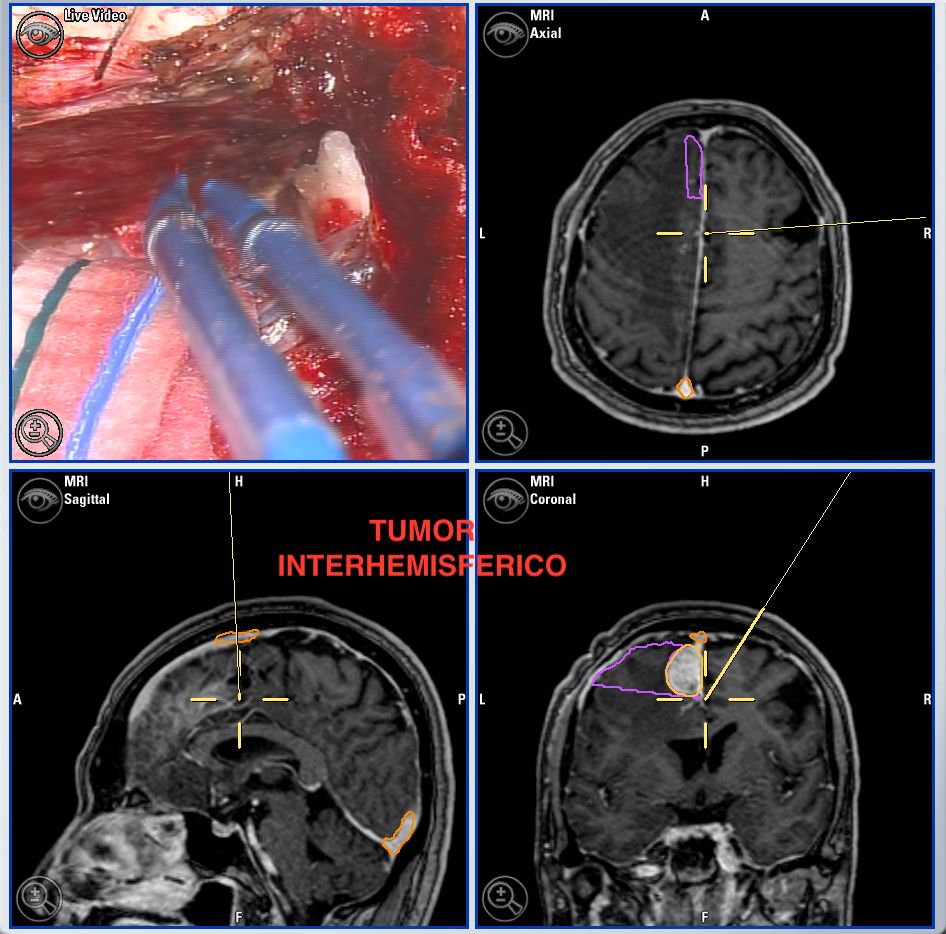

Microcirugía de base craneal